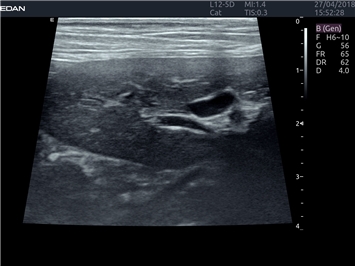

EDAN Acclarix LX4 VET

EDAN Acclarix LX4 VET представляет собой профессиональную ультразвуковую систему, специально разработанную для ветеринарных исследований. Сочетание стабильности, высокой производительности и эффективности делает эту систему идеальным выбором для современной ветеринарной практики.

• Адаптивная визуализация тканей:

• Оптимизация изображения для различных видов животных

• Улучшенная детализация структур

• Мультилучевое сложно-составное сканирование (SCI):

• Повышенная четкость изображения

• Улучшенная визуализация сложных анатомических структур